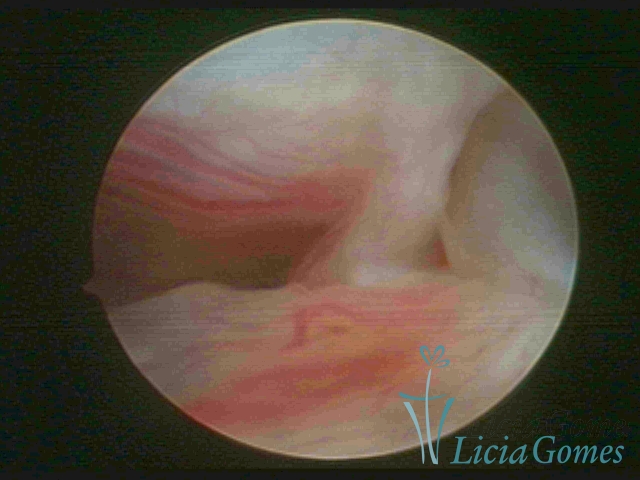

FIBROUS SYNECHIA

Uterine synechiae are scars (adherence) between the surface of the uterine walls, which may occur after the surgical procedure, uterine curettage, or after an inflammatory process in the uterine cavity (endometritis), which may lead to menstrual changes, infertility and obstetric complication such as abortion and premature birth.